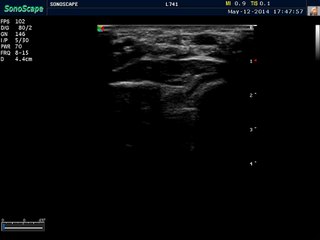

Sonoscape S8 Video of the Median Nerve for Carpal Tunnel Syndrome

The Sonoscape S8 HCU Color Doppler Diagnostic Ultrasound can help you view the Median Nerve for an accurate diagnosis. Purchase S8 unit at www.keebomed.com for a good price.